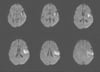

Ишемический инсульт в левой средней мозговой артерии (КТ)

На этом изображении КТ головного мозга без контрастирования видна уплотнённая левая средняя мозговая артерия. Этот признак указывает на локализованный сгусток в левой средней мозговой артерии (стрелка).

Image courtesy of Ji Y. Chong, MD.

Острый ишемический инсульт в левой островковой и лобной доле (МРТ)

На данном МРТ-скане показана область ограниченной диффузии, соответствующая острому ишемическому инсульту в островковой и лобной долях слева.